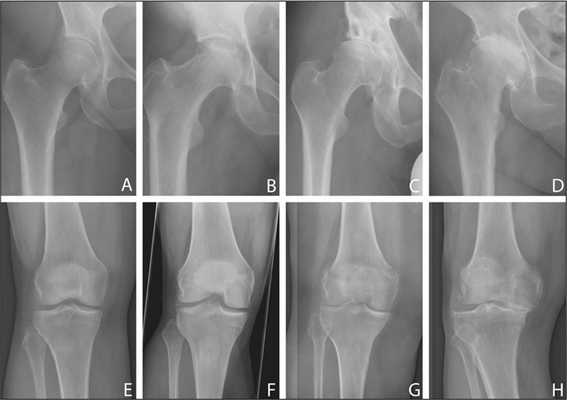

Важнейшим исследованием, имеющим решающее значение при постановке диагноза болезнь Пертеса, является рентгенография тазобедренного сустава. При подозрении на данное заболевание выполняются не только снимки в стандартных проекциях, но и рентгенограмма в проекции Лауэнштейна. Рентгенологическая картина зависит от стадии и выраженности болезни. Существуют различные рентгенологические классификации, наиболее популярными из которых являются классификации Кэттерола и Сальтера-Томсона.

- 1 группа. Рентгенологические признаки болезни Пертеса слабо выражены. Выявляется небольшой дефект в центральной или субхондральной зоне. Головка бедра имеет нормальную конфигурацию. Изменения в метафизе отсутствуют, линия перелома не определяется.

- 2 группа. Контуры головки не нарушены, на рентгенограмме видны деструктивные и склеротические изменения. Есть признаки фрагментации головки, определяется формирующийся секвестр.

- 3 группа. Головка поражена практически полностью, деформирована. Выявляется линия перелома.

- 4 группа. Головка поражена полностью. Выявляется линия перелома и изменения вертлужной впадины.

- 1 группа. Субхондральный перелом определяется только на рентгенограмме в проекции Лауэнштейна.

- 2 группа. Субхондральный перелом виден на всех снимках, наружная граница головки не изменена.

- 3 группа. Субхондральный перелом «захватывает» наружную часть эпифиза.

- 4 группа. Субхондральный перелом распространяется на весь эпифиз.